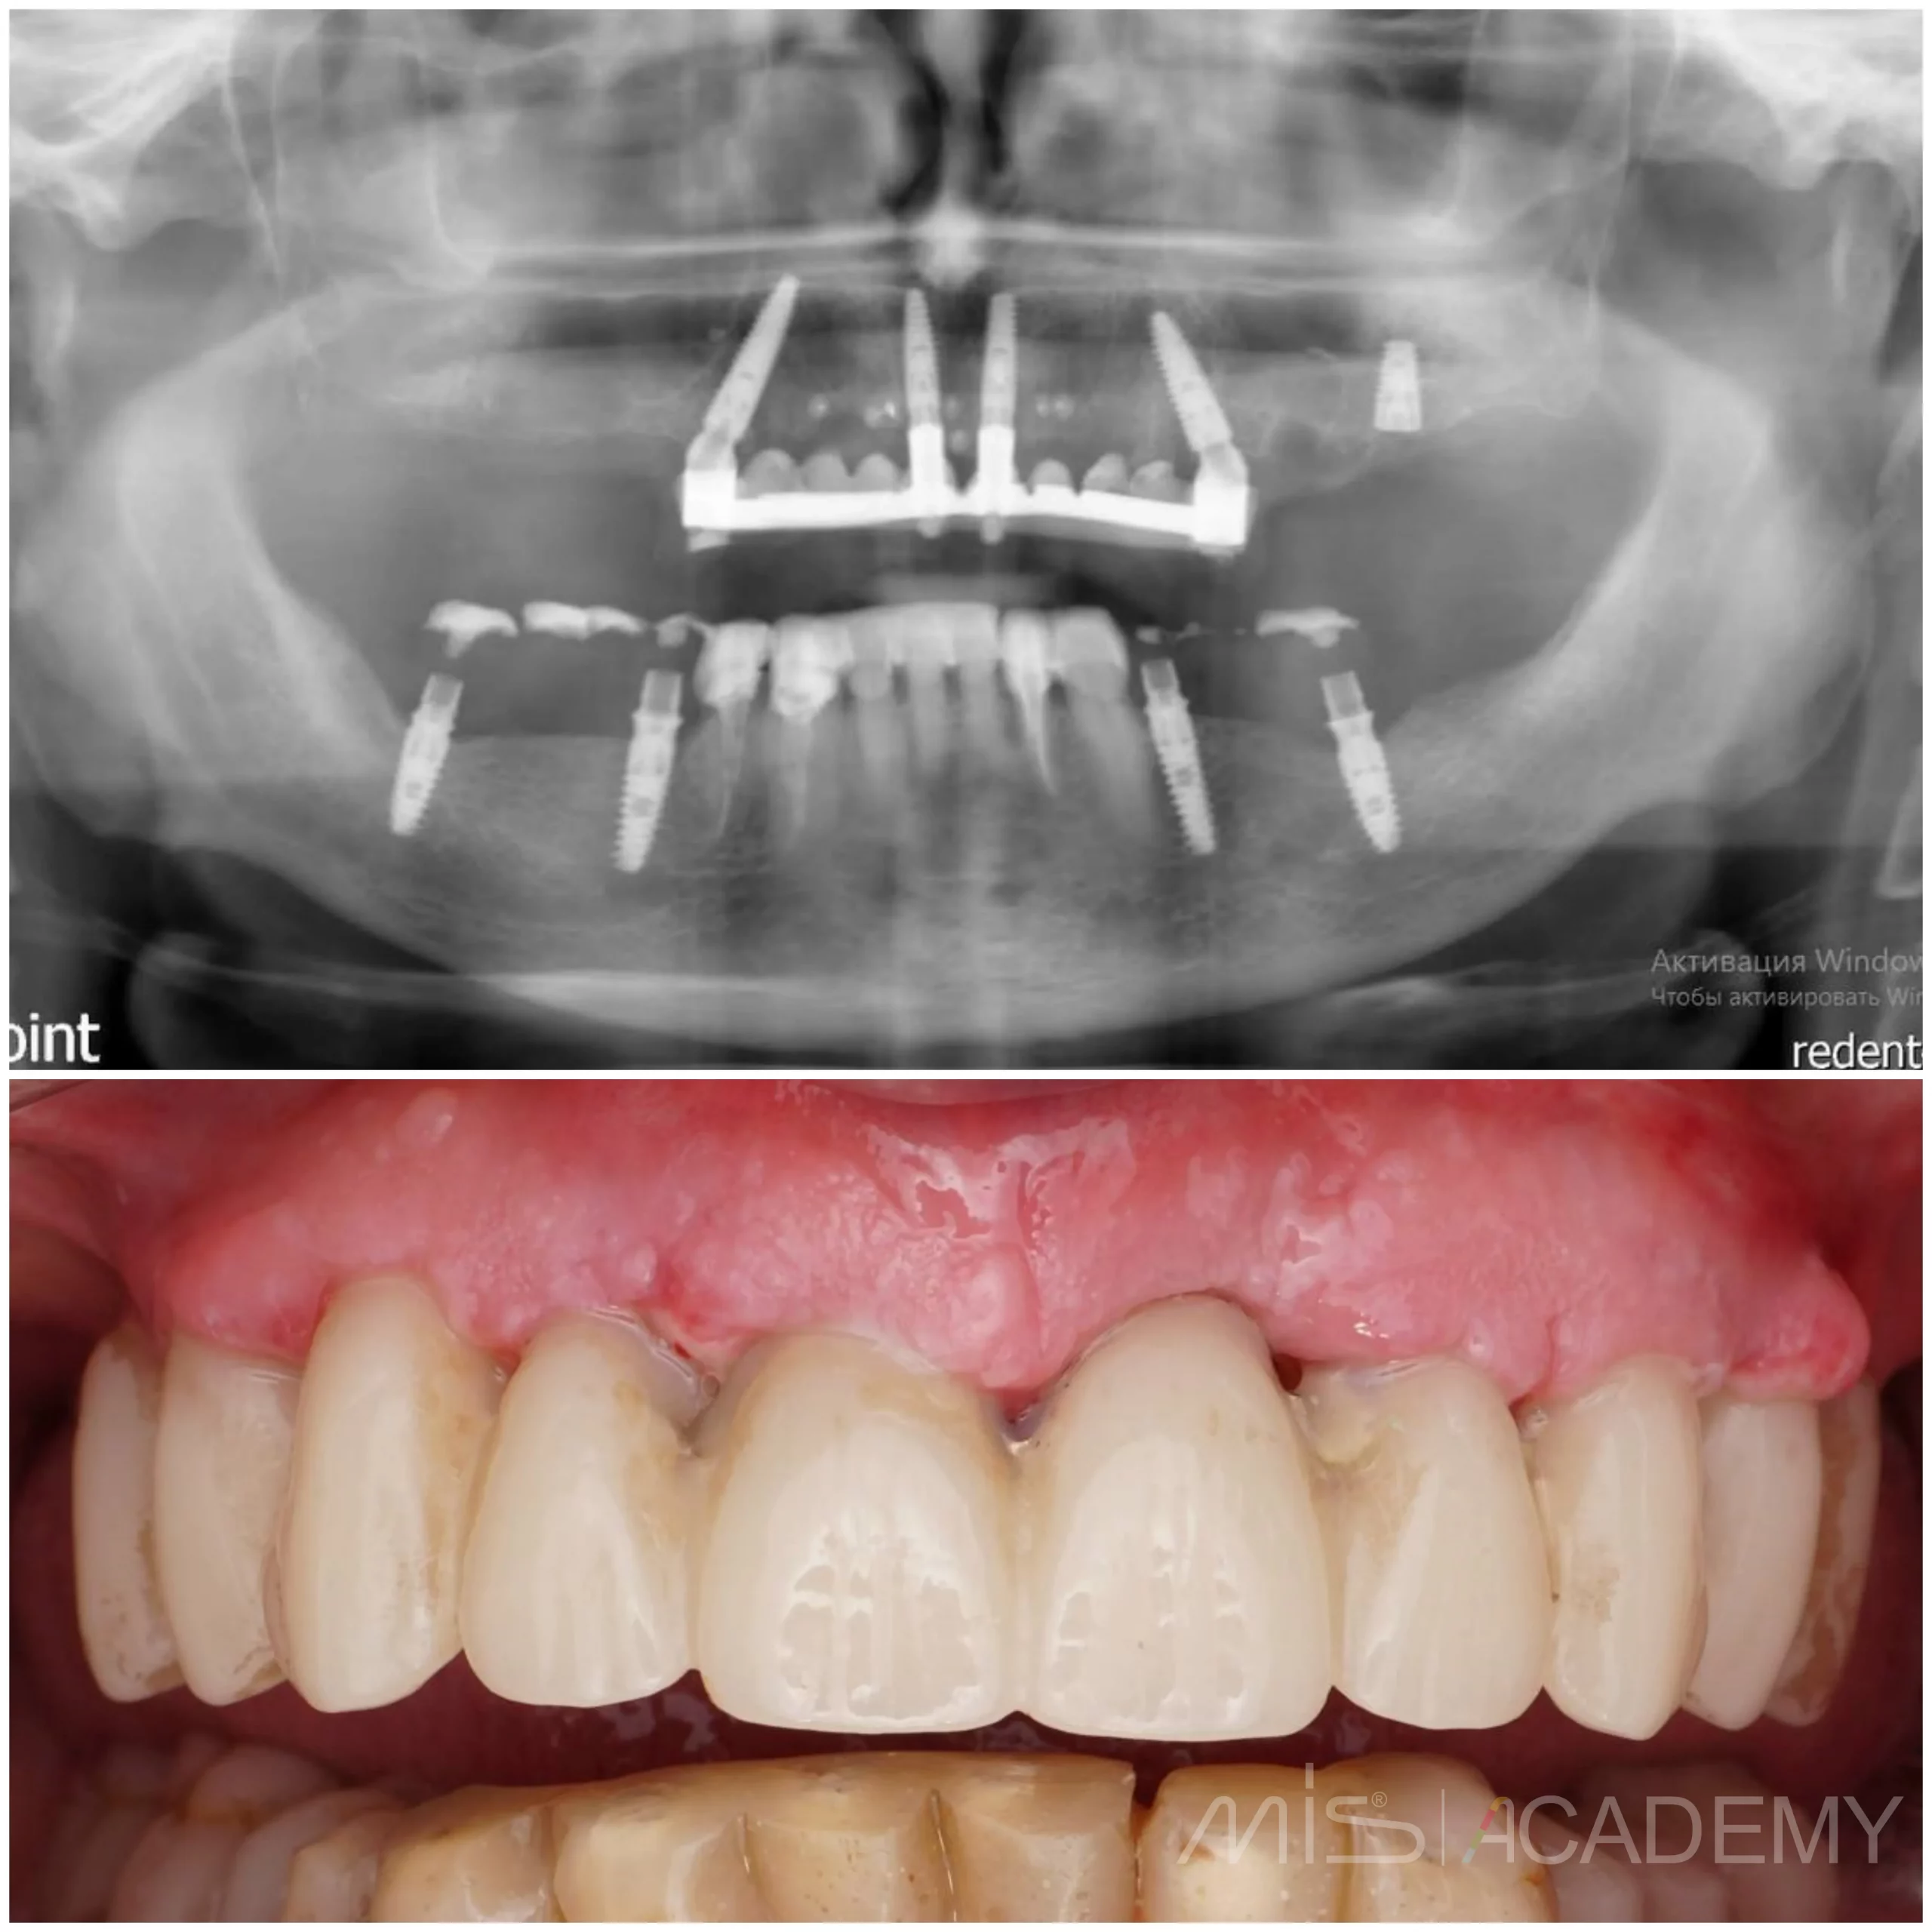

Тотальная реабилитация на верхней челюсти

Планирование и техническая часть: Игорь Лёвушкин

Ортопед: Алексей Калашников

В подобных случаях мы планируем накостные, либо гибридные шаблоны и преимущественно из металла.

— Удаление всех несостоятельных зубов на верхней челюсти.

— Установлены имплантаты Mis C1 и два открытых синус лифтинга в дистальных отделах.